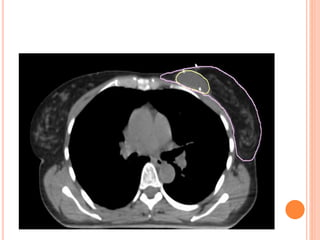

ROLE OF IMRT IN BREAST CANCER

IMRT BREAST: WHY?

(1) Better dose homogeneity for whole breast RT

(2) Better coverage of tumor cavity

(3) Feasibility of SIB

(4) Decrease dose to the critical organs

(5) Left sided tumors- decrease heart dose

 Reduces the hotspots specially in the superior and

inframammary portions of the breast.

Increases homogenity

Manifests clinically into decrease in moist

desqumation in these areas.

 With IMRT - better conformation of dose to target

tissues, increased sparing of normal tissues , limiting

dose to lungs & heart

 Studies have shown – 50% reduction in cardiac

mortality rate

 %age of ipsilateral lung volume receiving >20% of

isocentre dose can be decreased to 3.4%